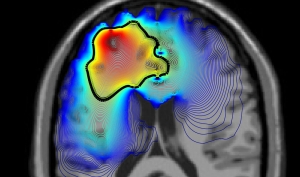

Brain scan image